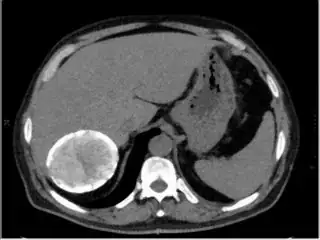

Below I apply two successive morphological openings to the image using a 3x3 circular kernel, and then apply k-means clustering to the gray levels. From your sample images and some I found on the internet, I decided to set k = 4. If you are using high-resolution images, first downsample them to dimensions ~400-600. Otherwise the morphological operation may not have a significant effect, and the k-means will be slow.

Below are some of the opened and segmented images. Of course there's more to be done in terms of

- separating out the liver region

- generalizing this to a large dataset

but hope this is at least a starting point.